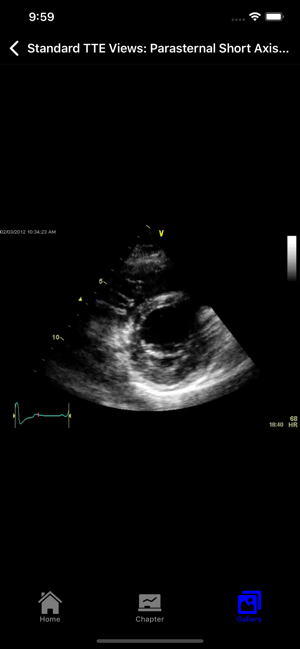

EchoSource (from the creators of ECGsource and CathSource) is a medical reference devoted exclusively to echocardiography. Developed by practicing cardiologists for both specialists and trainees in the field of cardiovascular disease, EchoSource offers the following content:* Searchable index of specialized topics including: History of EchocardiographyTransthoracic Echo – Learning the ProcedureTransesophageal Echo – Learning the ProcedureStandard Transthoracic Echocardiography ViewsStandard Transesophageal Echocardiography ViewsHemodynamics: Doppler OverviewHemodynamics: Color Flow ImagingHemodynamics: Transvalvular GradientsHemodynamics: Intracardiac PressuresHemodynamics: Cardiac Flow & the Continuity EquationHemodynamics: Proximal Isovelocity Surface Area (PISA)Left Ventricle: Systolic FunctionLeft Ventricle: Diastolic Function Valvular: Aortic StenosisValvular: Aortic RegurgitationValvular: Mitral StenosisValvular: Mitral RegurgitationValvular: Pulmonic StenosisValvular: P